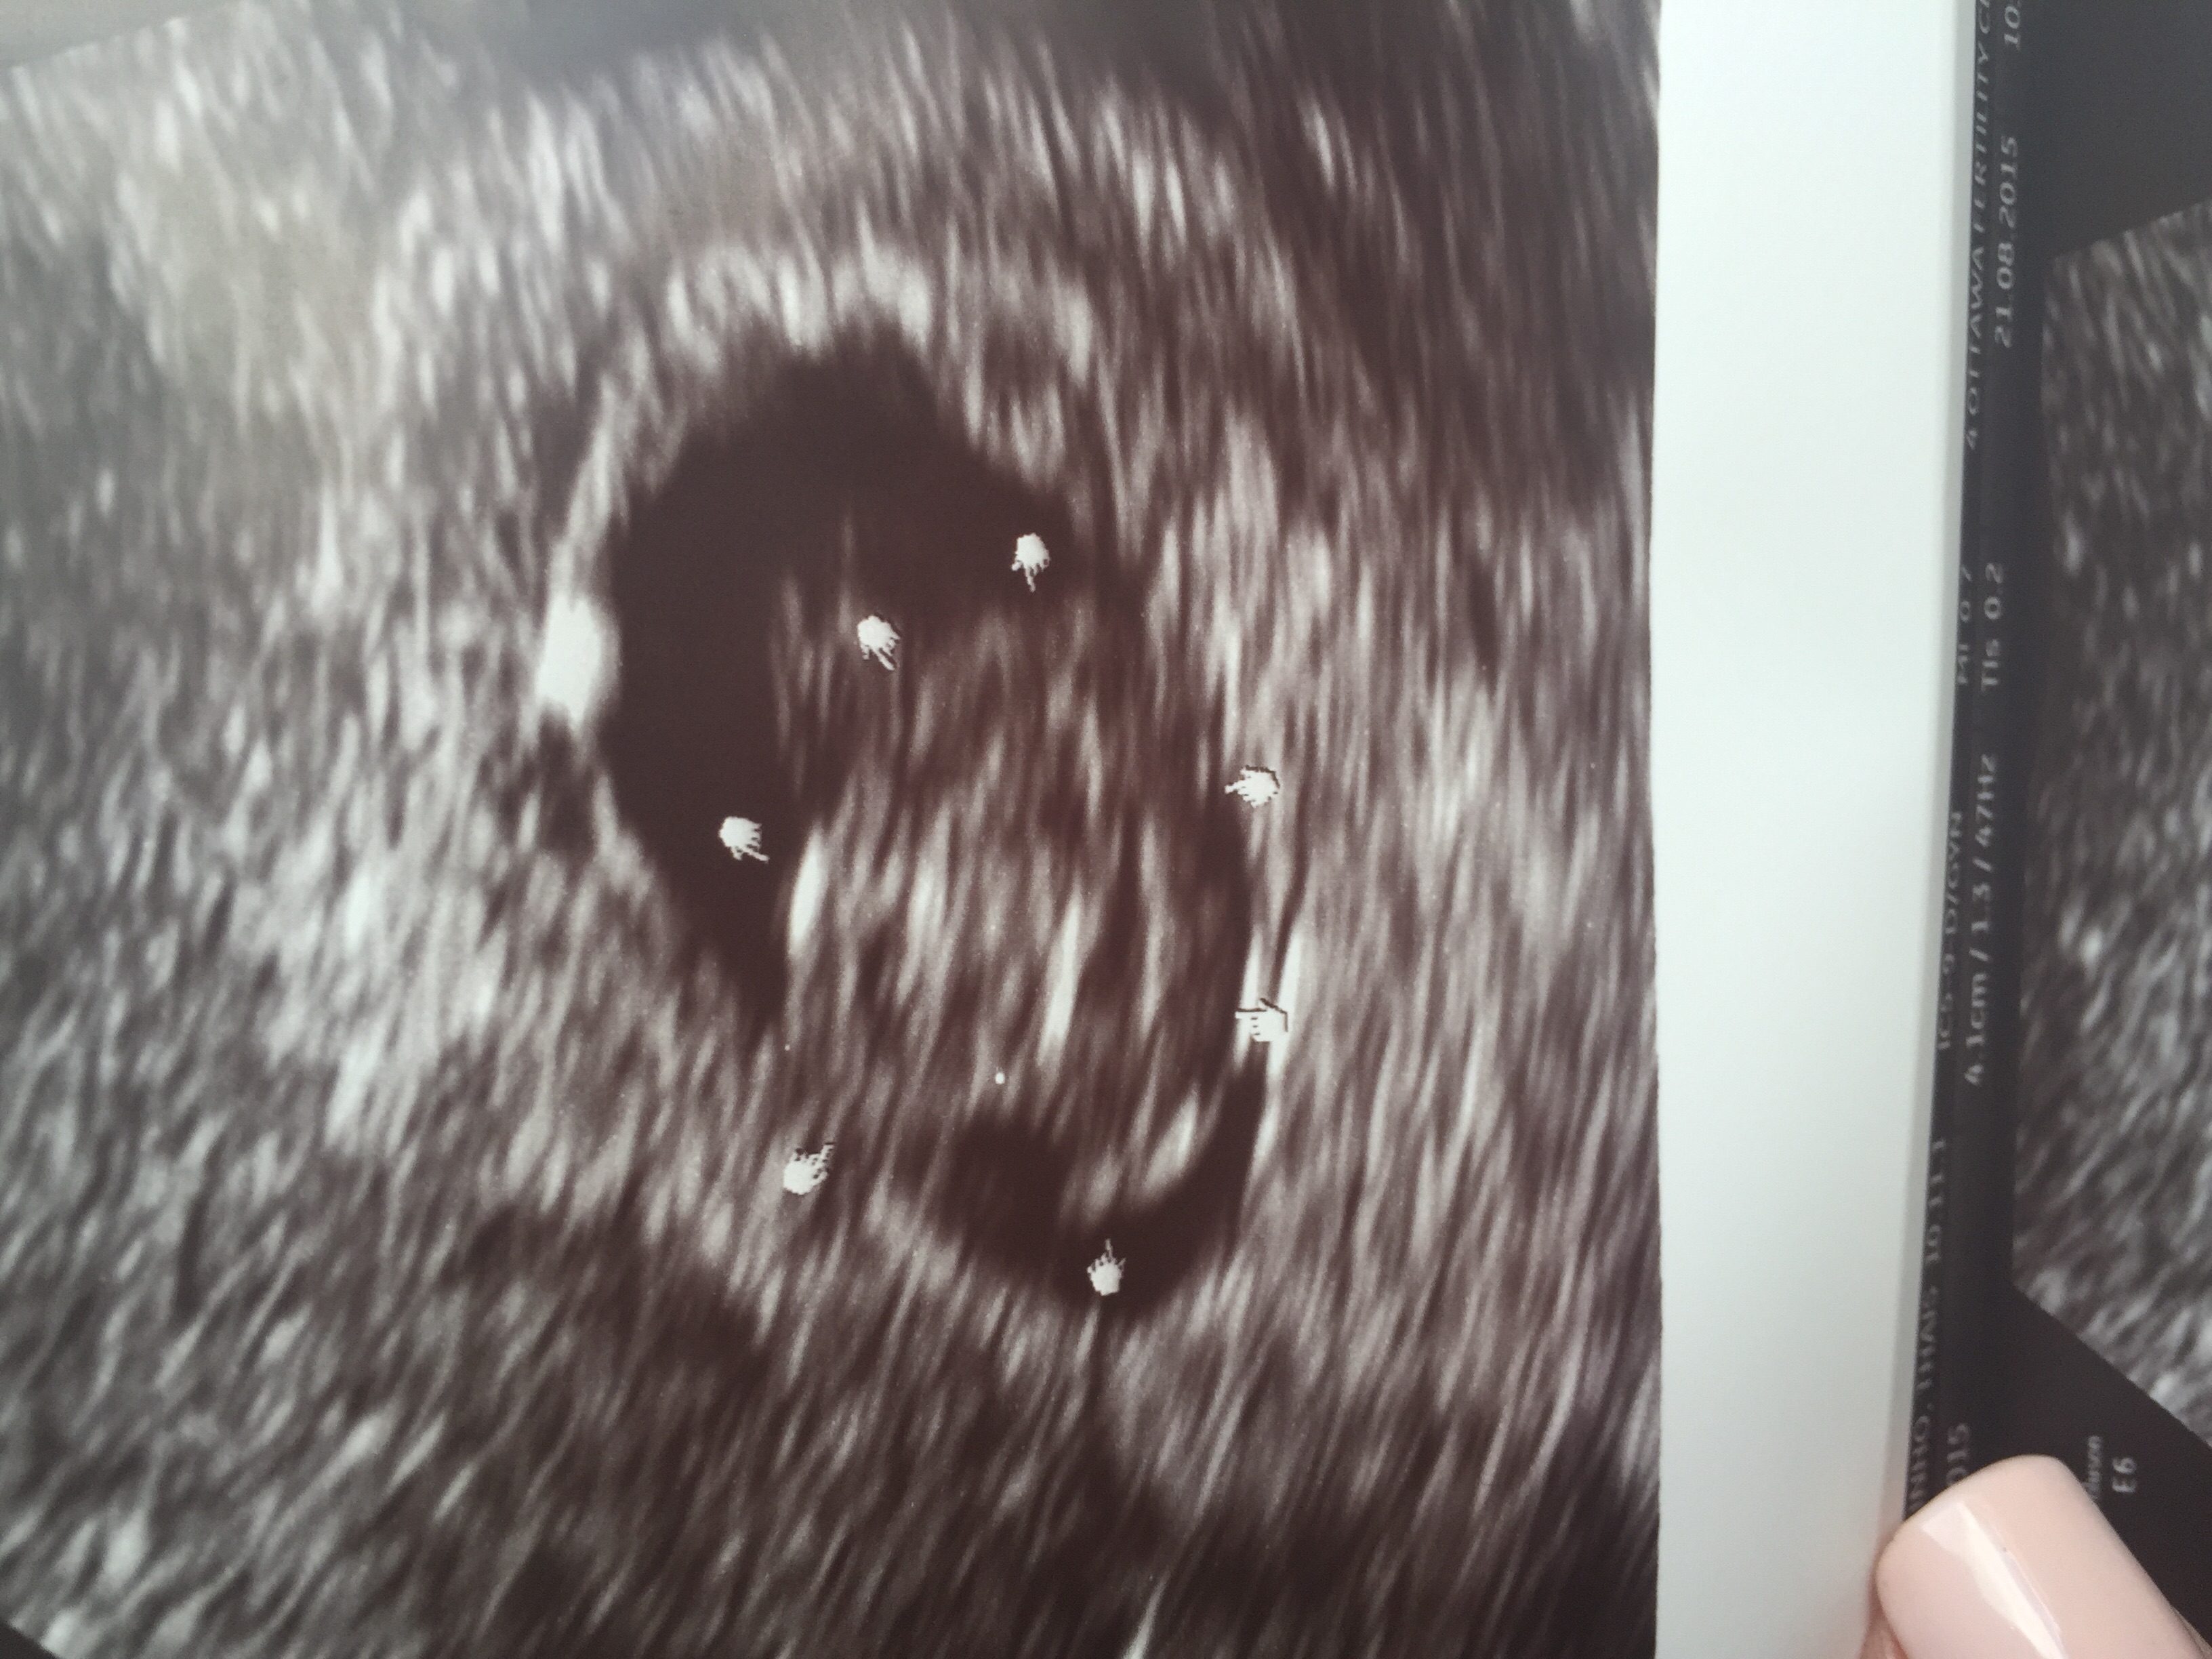

Woke up this morning with a tiny amount of brown spotting. Since I've miscarried before, I decided to call my dr and they were able to squeeze me in for an ultrasound early this AM. Low and behold a baby measuring exactly 6 weeks, 6 days which is where it should be. They saw a heartbeat too! I'm so overjoyed, and am celebrating that I am pregnant TODAY and trying to not think too much about the future. Bleeding has since stopped. She said could have been from intercourse or heavy lifting. Here's our bean: